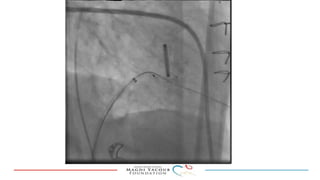

This document provides an overview of percutaneous prosthetic valve leakage (PVL) closure, including indications, approaches, techniques, and closure devices. It discusses that over 210,000 prosthetic valve surgeries are performed each year, with PVL occurring in some cases. While surgical closure has a high mortality rate, percutaneous closure has a procedural success rate of 86% and less complications. Indications for closure include symptomatic heart failure, hemolysis, rocking prosthesis, or leaks over 30% of the sewing ring. Techniques discussed include retrograde and transapical approaches using devices like the Amplatzer and Occlutech plugs. A team approach and techniques like sequential deployment are emphasized for